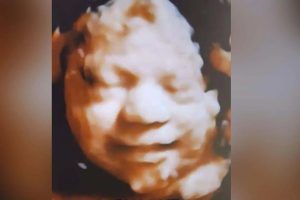

Embarazo, antes de que muchas mujeres siquiera sepan que están embarazadas.La ley se aprobó el año pasado, pero un juez bloqueó su adopción.